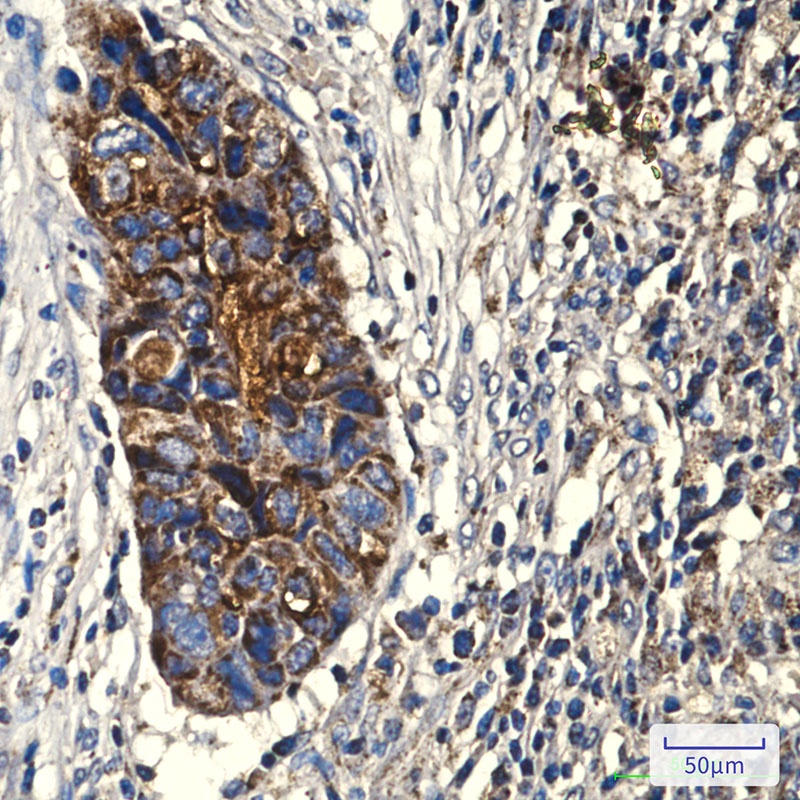

COX IV (4D2) Mouse mAb抗体

COX IV (4D2) Mouse mAb

COX4I1

ICC, IF, IHC-Fr, IHC-P, WB

Human, Mouse, Rat

Recombinant Protein of Cytochrome c oxidase subunit 4 isoform 1, mitochondrial

分子量:Calculated MW: 20 kDa; Observed MW: 17 kDa

应用稀释比例:WB: 1/1000 IHC: 1/50-1/200 IF: 1/100-1/200